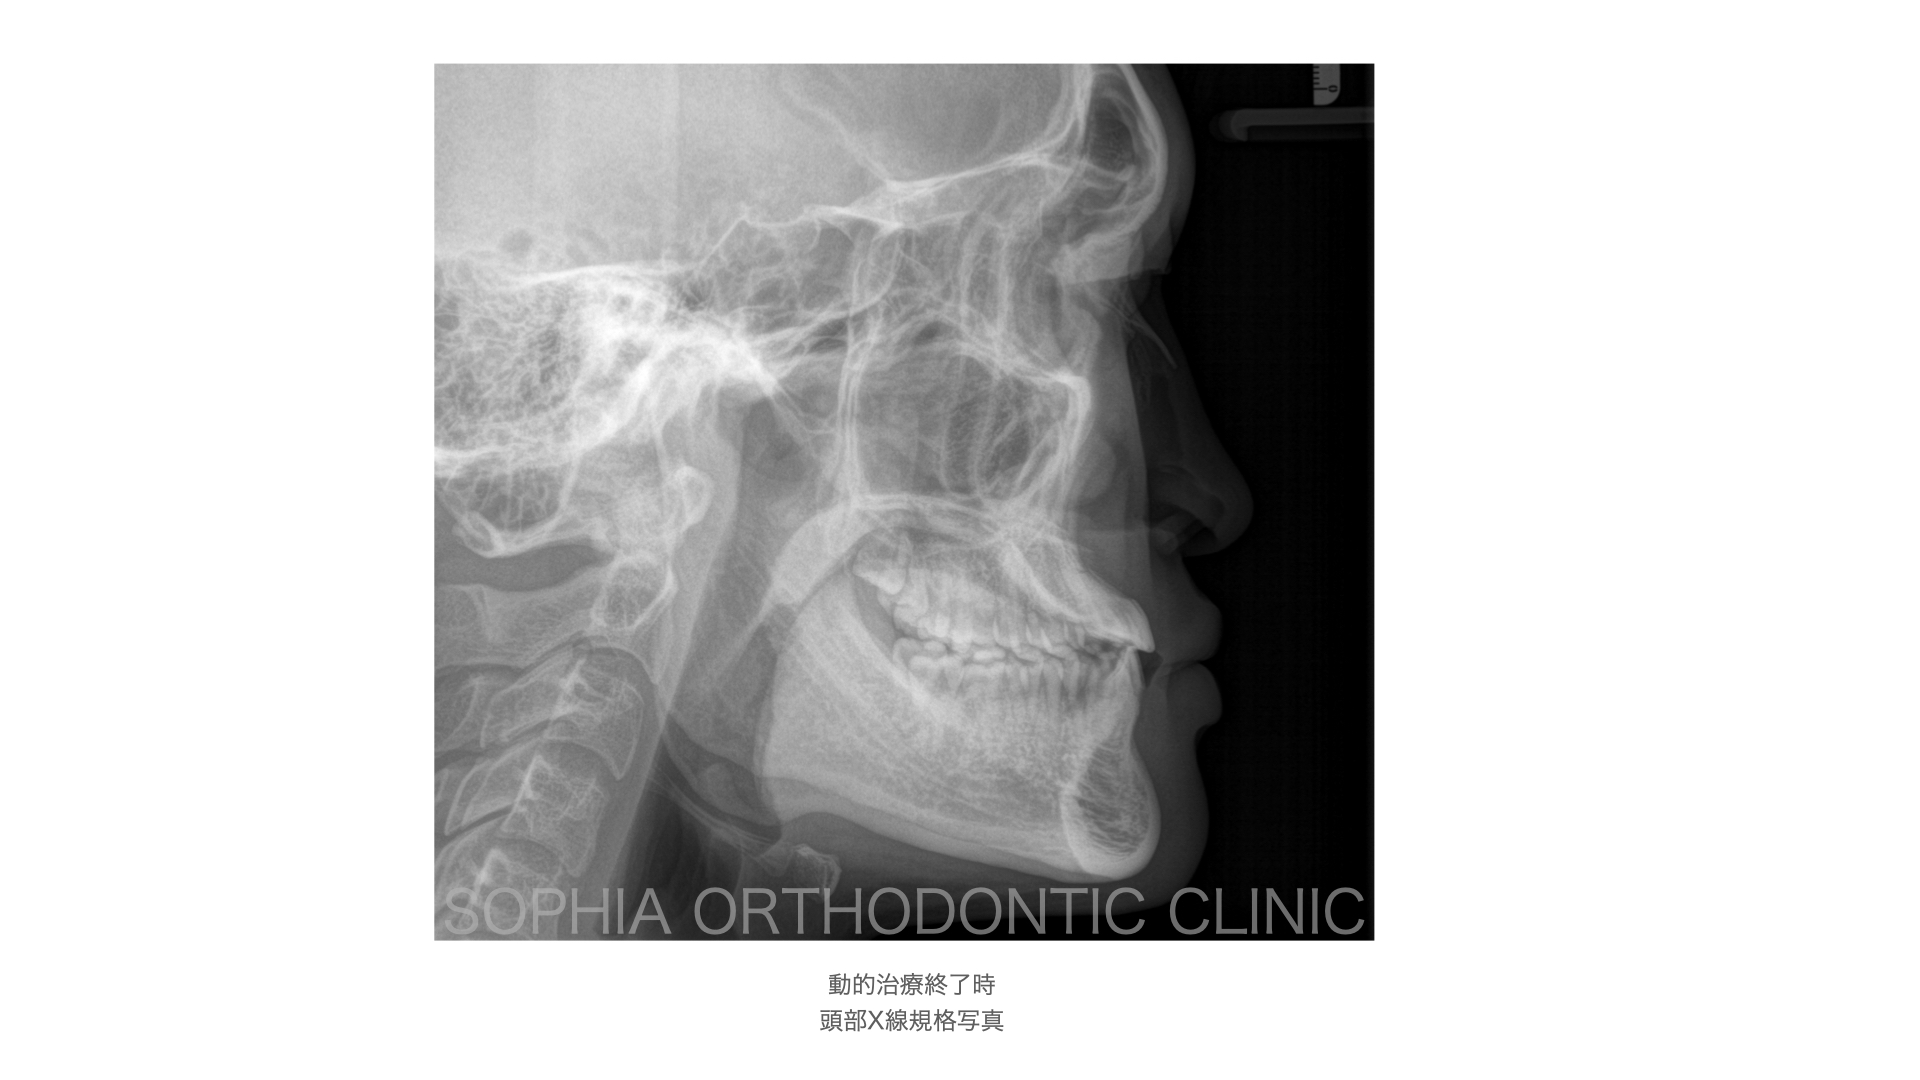

反対咬合.008